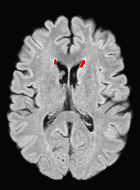

Patch size is another important parameter of the network. In computer vision applications such as object detection, usually a whole 2D image is used as a feature. However, full 3D medical images can not typically be used because of memory limitations. Fig. 4 shows examples of lesion memberships obtained with different sized 2D patches. As the patch sizes increases, the false positives that are mostly observed in the cortex tend to decrease. Fig. 5 shows a plot of Dice and LFPR with various patch sizes, ordered from left to right according to their increasing size. Note that smaller patches ( to ) produced significantly lower Dice and higher LFPR compared to other patches (), as seen from the memberships in Fig. 4. Also some of the highest Dice and lowest LFPR were observed for patches with large in-plane size, i.e., , , and . It was observed in Fig. 5 that there is no significant difference between Dice coefficients for , , or , but LFPR of both and are significantly lower than that of (). We chose as the optimal patch size. Other choices of smaller and patches (not shown) yielded worse results. Note that although training was performed with different patch sizes, the memberships were generated slice by slice, as the trained model consisted only of convolutions and did not need any information about patch sizes.